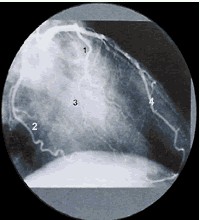

左前斜位:右冠状动脉![]() |

右冠状动脉象字母 “C” 1、右冠状动脉 2、右心室支 3、后降支 4、后侧支 |

|